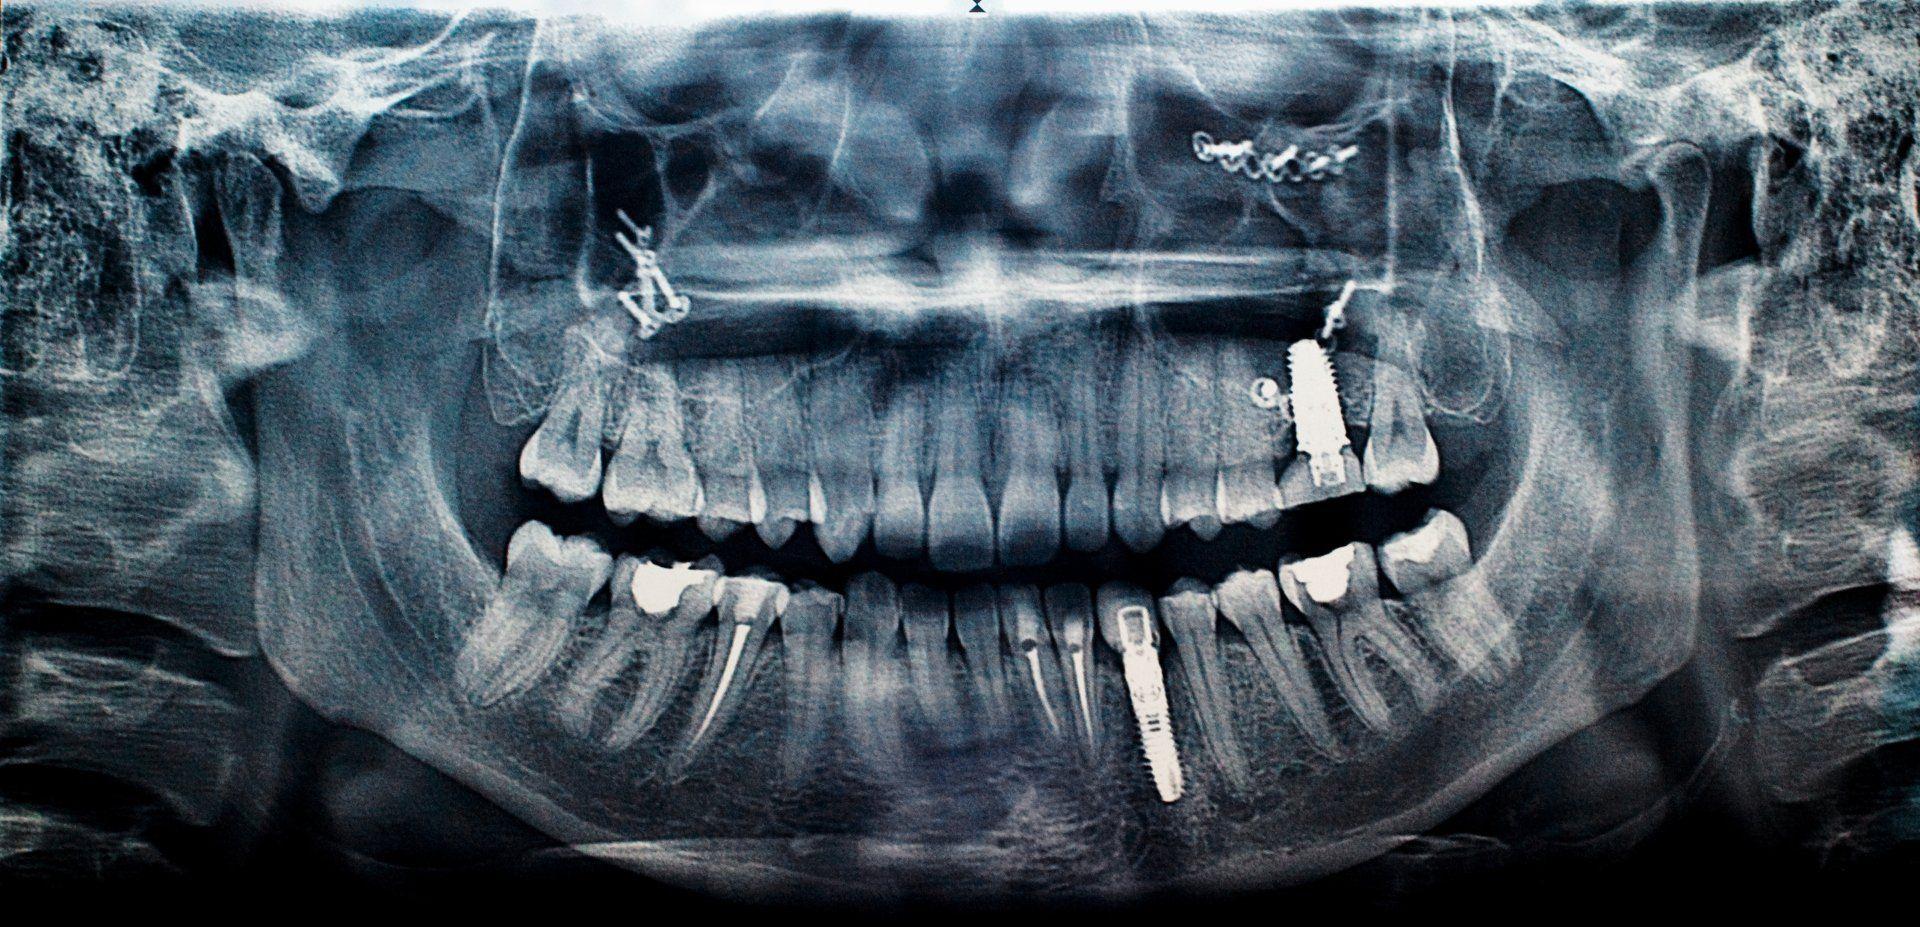

Implantologia

Grazie all’utilizzo di sistemi di implantologia di ultima generazione, lo studio è in grado di intervenire in maniera poco invasiva.

L’implantologia dentale consiste in nell’inserire una o più piccole viti di titanio – un materiale assolutamente biocompatibile e anallergico – realizzate su misura al fine di sostituire la radice di un dente naturale.

- implantologia

- é possibile eseguire protesi toronto su impianti: protesi dentale fissa totale che sostituisce un’intera arcata dentale avvitandosi stabilmente su 4-6 impianti inseriti chirurgicamente nell’osso mascellare o mandibolare, spesso realizzabile in tempi brevi (carico immediato).